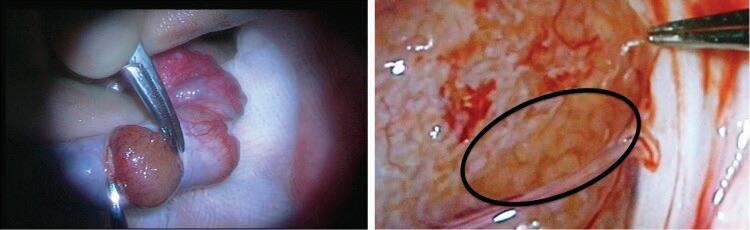

48 ГИГАНТСКИ КАВЕРНОЗЕН

ХЕМАНГИОМ НА ДЯСНО

ПРЕДСЪРДИЕ, СЪЧЕТАН С ЧЕРНОДРОБЕН ХЕМАНГИОМ

И. Тодоров